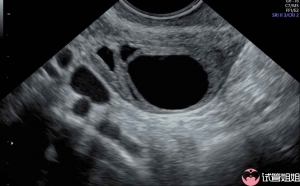

子宫情况

准妈妈卵泡个数